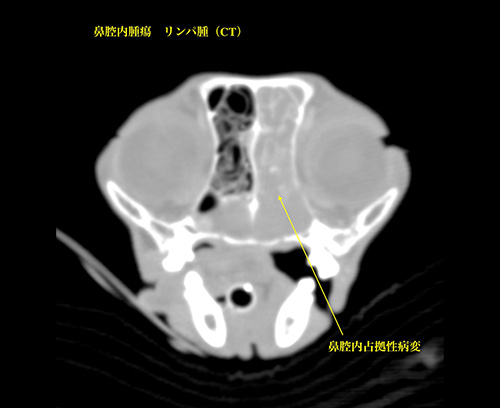

鼻腔内腫瘍(リンパ腫)

鼻腔内腫瘍(腺癌)